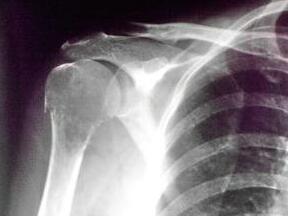

来到我院后,王怀庆主任再初步掌握胡女士的情况后,为她安排了进一步的检查。检查结果:血常规呈小细胞低色素性贫血;血沉140mm/h,C-反应蛋白22.3ng/ml;血钙2.13mmol/l,血镁1.66mmol/l,血磷正常,碱性磷酸...[详细]